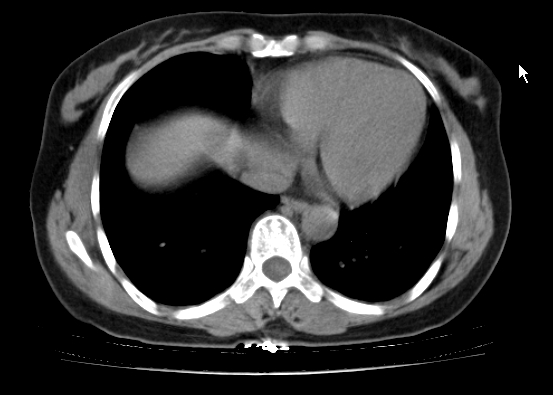

标题: CT25227:背部疼痛伴双侧胸壁痛2月,食欲差。 [打印本页]

标题: CT25227:背部疼痛伴双侧胸壁痛2月,食欲差。

肺结核并胸椎结核?请各位高手指教。

用椎体的条件来扫胸椎呀!考虑1左侧胸膜小结节形成2椎体结核并冷脓肿形成

考虑胸椎结核并椎旁软组织肿胀。

左肺结核灶,胸椎结核并冷脓肿。

左肺结核灶,胸椎结核并冷脓肿

食道癌并胸椎及肺内转移